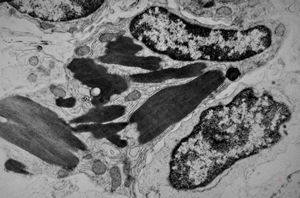

jejunal mucosa - contracted smooth muscle cells

contracted smooth muscle cells in an intestinal villus